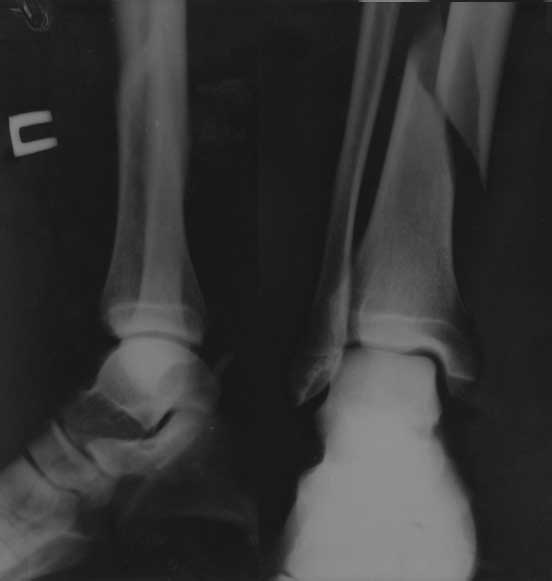

[Ortho] Повторный перелом н/3 большеберцовой кости с наличием металлофиксаторов

Первичный рентген